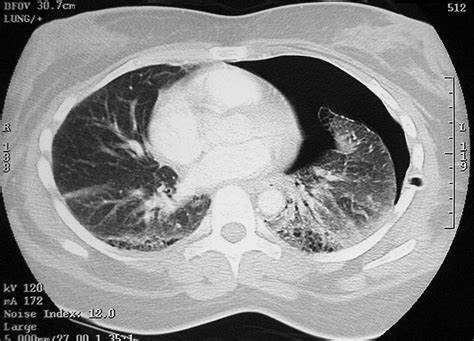

- CT scan

- Pneumonia

- Asthma

- Chronic obstructive pulmonary disease

- Restrictive lung disease

- Pneumothorax

- Pulmonary embolism

- Congestive heart failure